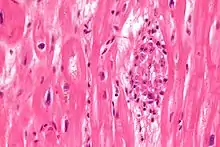

| Aschoff bodies are microscopic structures seen in patient with rheumatic fever | |

In medicine, Aschoff bodies are nodules found in the hearts of individuals with rheumatic fever. They result from inflammation in the heart muscle and are characteristic of rheumatic heart disease. These nodules were discovered independently by Ludwig Aschoff and Paul Rudolf Geipel, and for this reason they are occasionally called Aschoff–Geipel bodies.

Microscopically, Aschoff bodies are areas of inflammation of the connective tissue of the heart, or focal interstitial inflammation. Fully developed Aschoff bodies are granulomatous structures consisting of fibrinoid change, lymphocytic infiltration, occasional plasma cells, and characteristically abnormal macrophages surrounding necrotic centres. Some of these macrophages may fuse to form multinucleated giant cells. Others may become Anitschkow cells or "caterpillar cells," so named because of the appearance of their chromatin.

They are pathognomic foci of fibrinoid necrosis found in many sites, most often the myocardium. Initially they are surrounded by lymphocytes, macrophages, and a few plasma cells, but they are slowly replaced by a fibrous scar. Aschoff bodies are found in all the three layers of the heart, least chance in the pericardium.

The Aschoff nodules are foci of T lymphocytes, occasional plasma cells, and activated macrophages (Anitschkow cells) pathognomonic of rheumatic fever. These macrophages have abundant cytoplasm and central round nuclei in which chromatin condenses into a central, slender, wavy ribbon, the reason why they are sometimes called "caterpillar cells". They are especially found in the vicinity of small blood vessels in the myocardium and endocardium and occasionally in the pericardium, and also the adventitia of the proximal part of the aorta. Lesions similar to the Aschoff nodules may also be found in extra-cardiac tissues.